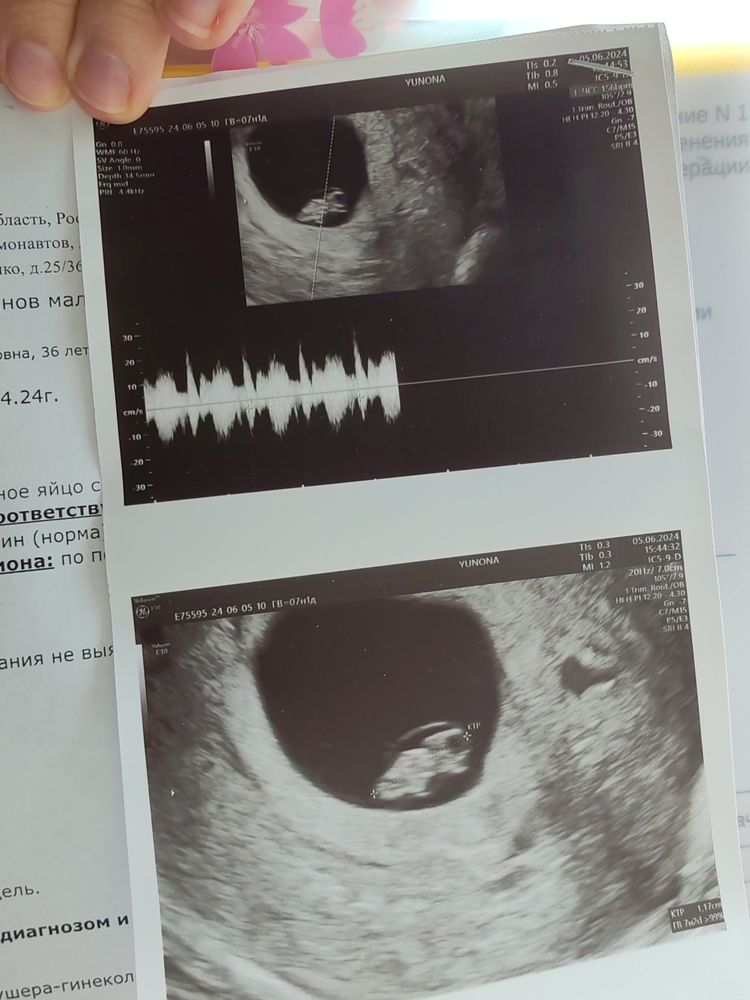

УЗИ трансвагинальное, срок 7,3 н